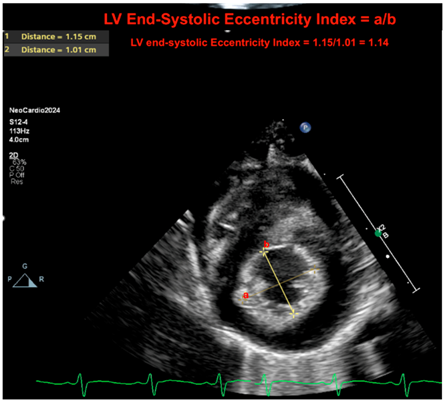

| LV eccentricity index at peak systole | The left ventricular (LV) end-systolic eccentricity index provides a quantifiable metric of septal deformation. The index is computed as the ratio of the diameter parallel to the septum to the diameter perpendicular to the septum at peak of systole. In a situation where there is a flat septal configuration or a bowing septum, this ratio will decrease. This provides a continuous quantifiable metric of the “septal motion.” In the absence of a congenital cardiac anomaly, ventricles will equalize pressure with their corresponding outflow tract at the peak of systole. As such, the RV–LV relationship may inform on the systemic-to-pulmonary systolic pressure relationship. In the expected setting, the LV systolic pressure should be above the RV systolic pressure, and the LV should form a near-perfect circular configuration at the peak of systole. The left ventricular (LV) end-systolic eccentricity index (EI) ≥ 1.3 has been associated with PH in BPD infants [29,30]. |

| Eccentricity index | ![]() |

| Legend: The LV end-systolic eccentricity index provides a quantifiable metric of septal deformation. The index is computed as the ratio of the diameter parallel to the septum to the diameter perpendicular to the septum at peak of systole. In situations where there is a flat septal configuration or a bowing septum, this ratio will decrease. This provides a continuous quantifiable metric of the “septal motion.” In the absence of a congenital cardiac anomaly, ventricles will equalize pressure with their corresponding outflow tract at the peak of systole. As such, the RV–LV relationship may inform on the systemic to pulmonary systolic pressure relationship. In the expected setting, the LV systolic pressure should be below the RV systolic pressure, and the LV should form a near-perfect circular configuration at the peak of systole. Here, the ratio is 1.14 (normal if <1.3). Letters a = 1; b = 2. The equation is a/b. |